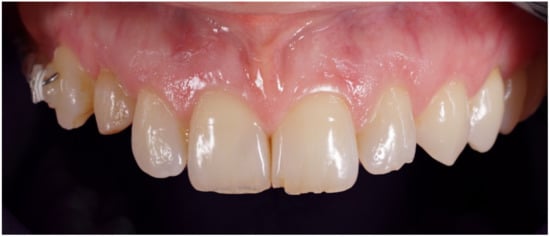

Figure 8.

Delivery of final crown.

Figure 9.

Definitive crown after 1 year of follow-up, frontal view.

Figure 10.

Periapical X-ray at 1 year of follow-up.